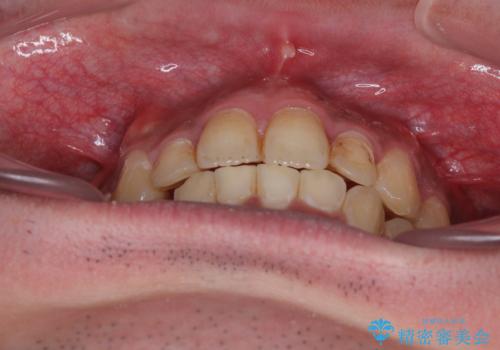

- 主張してる上の前歯を気にして来院された患者様です。

上の前歯が出ているものの、口元が出っ歯というわけではなかったため、非抜歯矯正にて治療を行うこととしました。

下顎に対して上顎歯列が全体的に前方に位置しており、特に右側の奥歯の咬み合わせの前後のズレが大きいため、補助装置を用いて咬み合わせを改善することとしました。

元々むし歯リスクが高かった上に、矯正治療中も磨き残しが多かったため、今後はむし歯治療を行う必要があります。